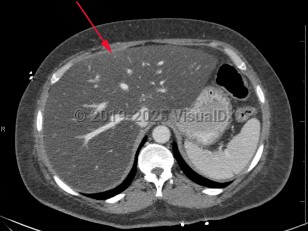

Metabolic dysfunction-associated steatotic liver disease

Screening for MASLD is of the utmost importance in patients with underlying risk factors, primarily obesity and metabolic syndrome, as it is often asymptomatic. Some patients report vague symptoms such as fatigue or mild right upper quadrant abdominal pain. If MASLD progresses to cirrhosis, patients will often present with signs and symptoms of advanced liver disease: spider angiomata, gynecomastia, ascites, jaundice, and peripheral edema.